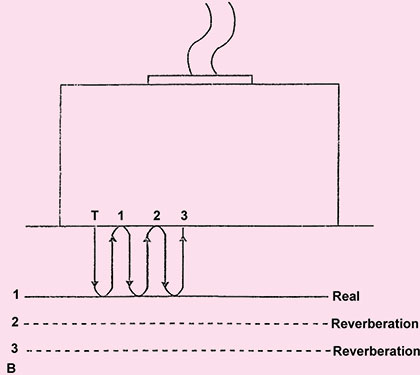

Reverberation

Reverberation occurs between transducer and a strong reflector or it can occur between two reflecting surfaces lying in the direction of beam. Here the reflector may be sufficiently strong to be detected by the instrument and to cause confusion on the display. The process by which they are produced is explained in Figure 1.21A. This result in the display of reflector that are not real.

Therefore not all echoes that originates at an acoustic interface return to the transducers without further reflection. If strongly reflecting boundaries are present sound wave can reflects back and forth before they eventually return to the transducer. This delay in registering the echo leads to reverberation. These reverberation echoes are projected as several parallel line placed beneath the real reflector at separate interval equal to separation between the transducer and real structure. And each subsequent echo is weaker than prior one, e.g. from intestinal gas to liver or ribs, urinary bladder or gallbladder. Reverberation can obscure tissue that lie behind the gas (Fig. 1.21B).